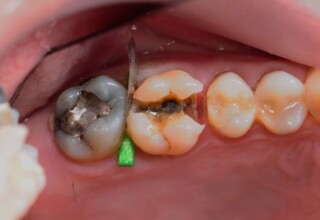

Αποκατάσταση Ραγισμένου Γομφίου με σφράγισμα Σύνθετης Ρητίνης

Τα ραγισμένα δόντια αποτελούν μια πρόκληση για την επανορθωτική οδοντιατρική από την άποψη της δυσκολίας της αποκατάστασης(συνήθως μεγάλα σφραγίσματα) άλλα κυρίως από τα προληπτικά μετρά που πρέπει να παρθούν για να αποφευχθεί ένα πλήρες κάταγμα. Η ακόλουθη περίπτωση παρουσιάζει την απλούστερη προσέγγιση της άμεσης συγκολλούμενης αποκατάστασης από σύνθετη ρητίνη. Βασίζεται στο σκεπτικό ενός συγκολούμμενου σφραγίσματος που «κρατάει» τα εναπομείναντα οδοντικά τμήματα «ενωμένα». Ο συγκεκριμένος γομφίος παρέμεινε ακέραιος για δυο χρονιά, οπότε χρειάστηκε απονεύρωση γιατί νεκρώθηκε και κατόπιν τοποθετήθηκε στεφάνη για αυξημένη προστασία.